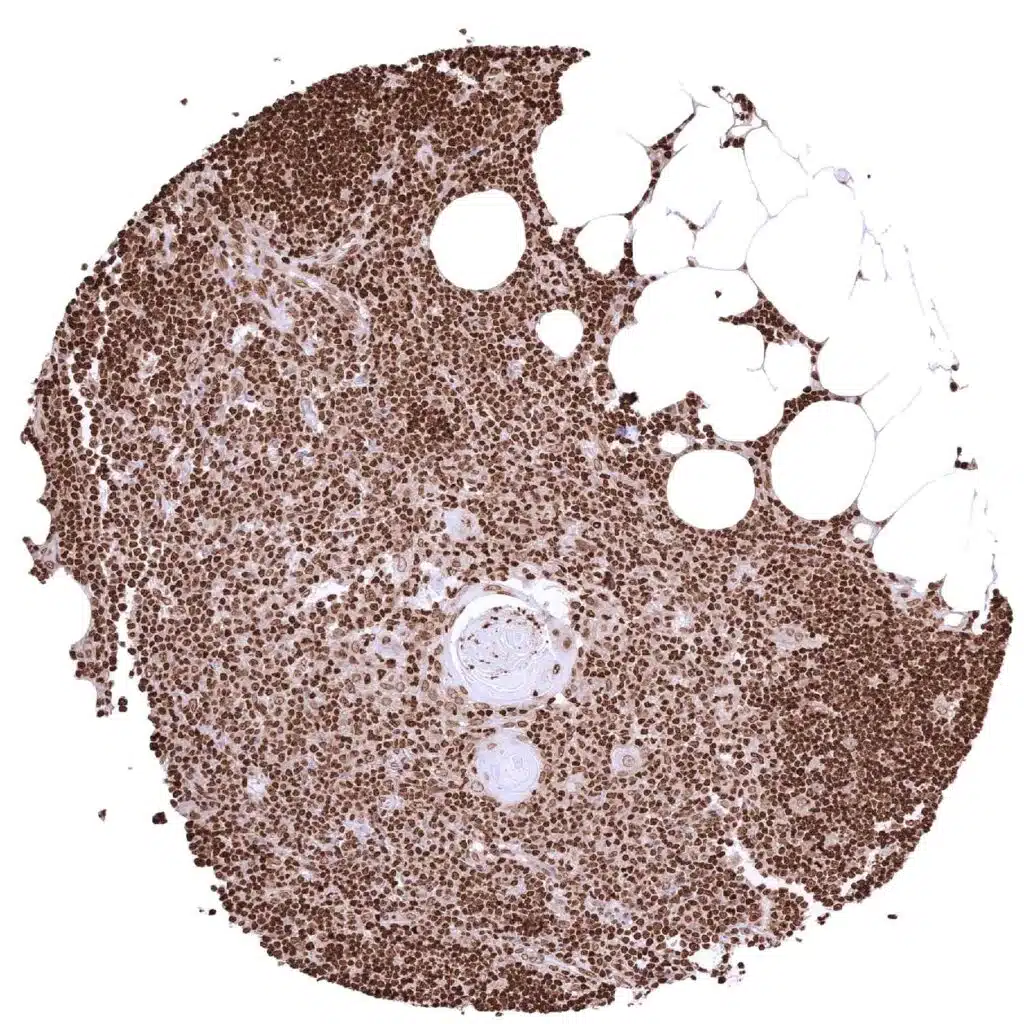

Histone H3 antibody [MSVA-903M] HistoMAX

Thymus

Thymus (2)